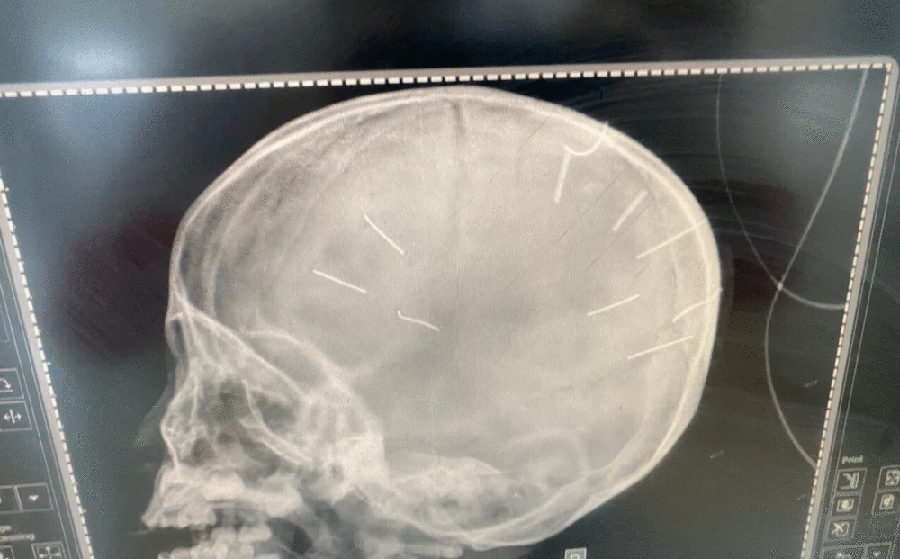

Cháu bé 3 tuổi có nhiều vật giống đinh ghim vào đầu đang nguy kịch

Công an triệu tập mẹ bé gái 3 tuổi có vật giống đinh ghim trong hộp sọ